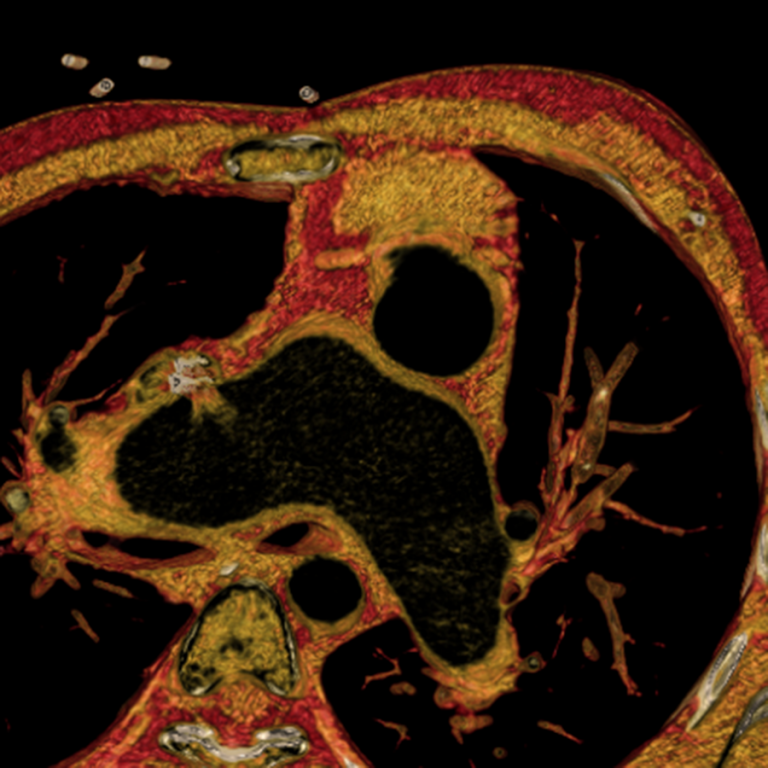

Thank you for your interest in cardiovascular imaging at the University of Wisconsin School of Medicine and Public Health, Department of Radiology. The Cardiovascular Imaging Section has long provided innovative, advanced clinical care in non-invasive cardiovascular imaging, including cardiac magnetic resonance imaging (MRI), magnetic resonance angiography (MRA), cardiac and coronary computed tomography (CCTA), and computed tomography angiography (CTA).

The volume of clinical studies has grown continuously and we now perform over 5000 non-invasive cardiovascular CT and MR studies each year. The members of our section are very active and renowned locally, nationally, and internationally with over 550 peer-reviewed publications, 30 book chapters, 1200 scientific presentations, and 50 patents. Time-resolved contrast-enhanced MRA (TRICKs), pulmonary MRA for pulmonary embolism, non-contrast-enhanced MRA, four-dimensional (4D) flow MRI, low-dose CTA and CCTA, and 3D printing are just a few examples of the innovations developed by our group that have had a significant impact on clinical care locally and beyond.